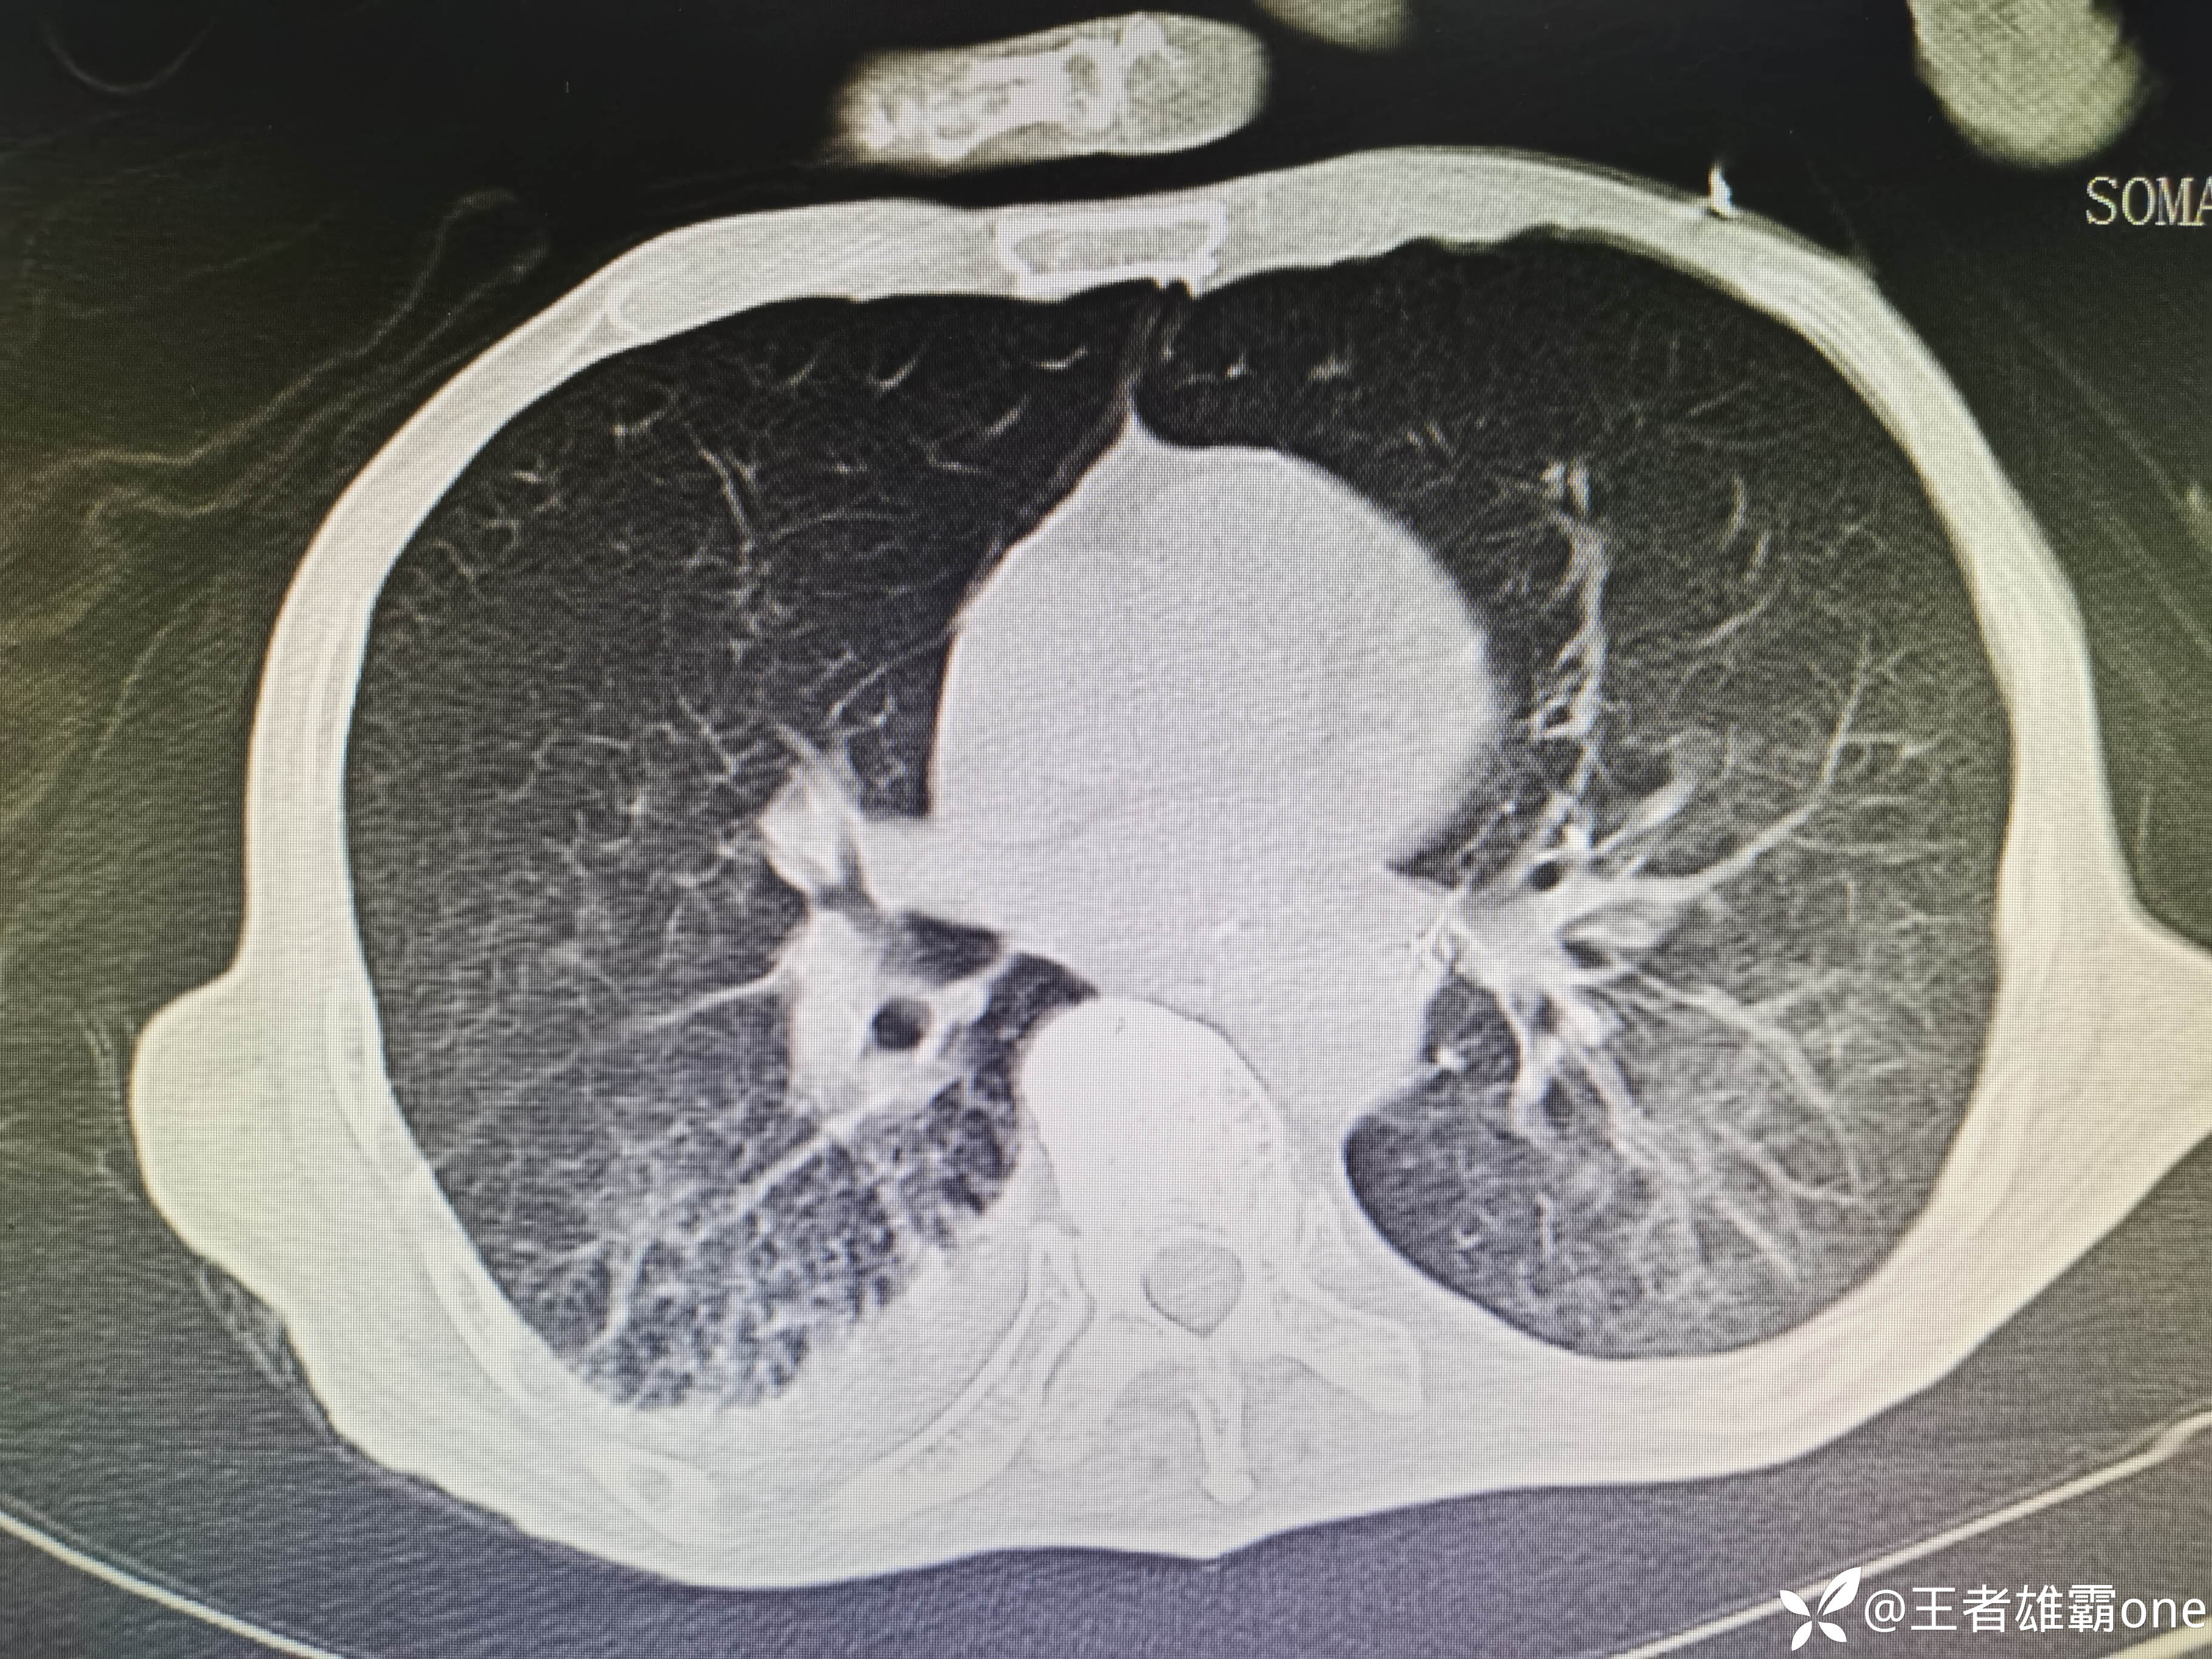

入院时胸部CT:

具体图片: